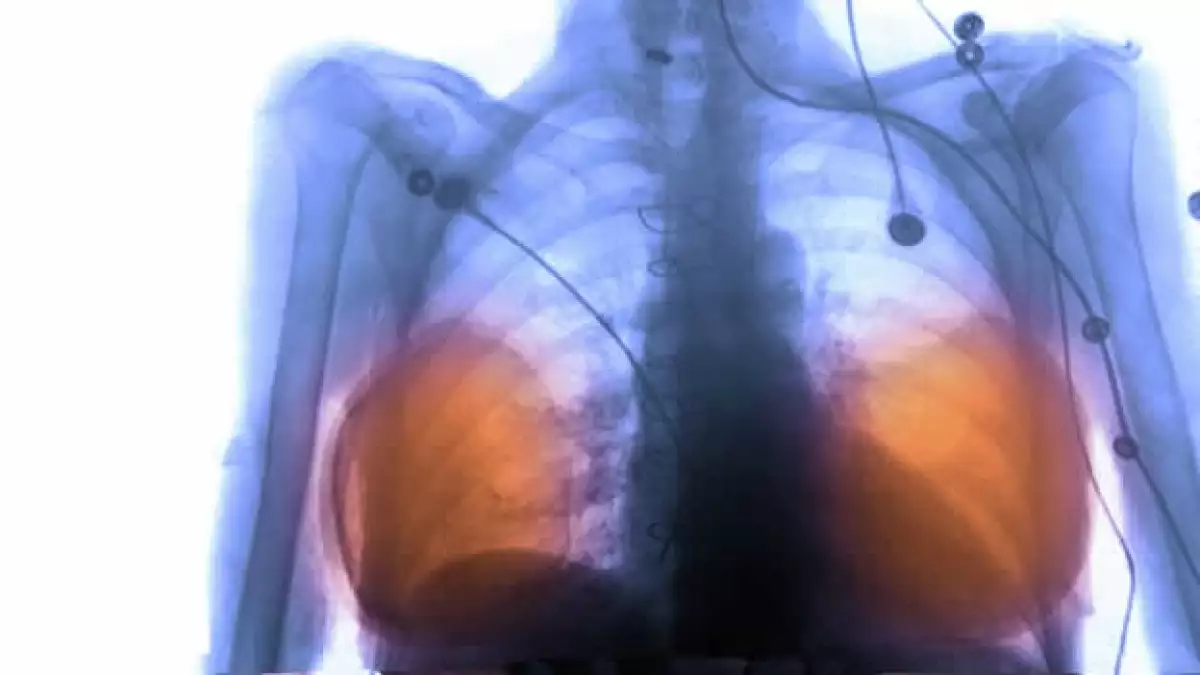

El gobierno francés pagará por la remoción de implantes de seno en decenas de miles de sus ciudadanas debido a preocupaciones por una posible relación con una rara forma de cáncer, informó el Ministerio de Salud este miércoles.

El ministerio dice que alrededor de 30,000 francesas tienen implantes de PIP, que actualmente no están aprobados para su uso en Estados Unidos.

La agencia del gobierno francés que evalúa la seguridad de los productos médicos informa que 523 mujeres se los han retirado desde que un defecto fue descubierto el año pasado.

Más de 1,000 implantes se han roto desde entonces, señala la agencia.